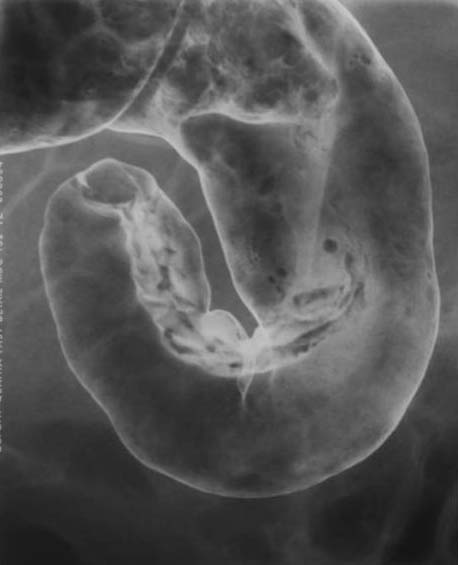

Patientin, 81 Jahre alt, mit starken abdominellen Beschwerden. Spiegelbildung

ist in der Abdomen-Übersichtsaufnahme zu erkennen.

Patient

mit Spiegelbildung in der Abdomenübersicht im Dünndarm (siehe auch

CT). Darm

im

Darm.

Invagination,

ileoileal